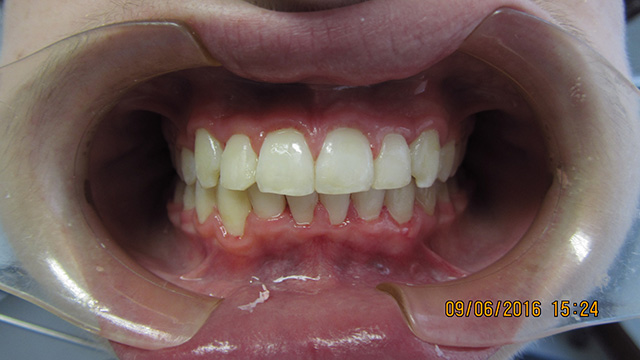

Ortodontzia, pilaketa ebakitzailea